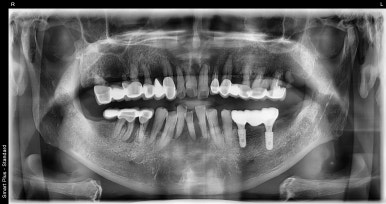

임플란트 수술 전후 모습

(전) 2022-08-23 (후) 2023-06-05

(전) 2022-08-23 (후) 2023-06-20

전후 사진을 보시면 텅 비어있던 왼쪽 아래부분이 임플란트 후 잘 채워져있는 것을 보실 수 있습니다.